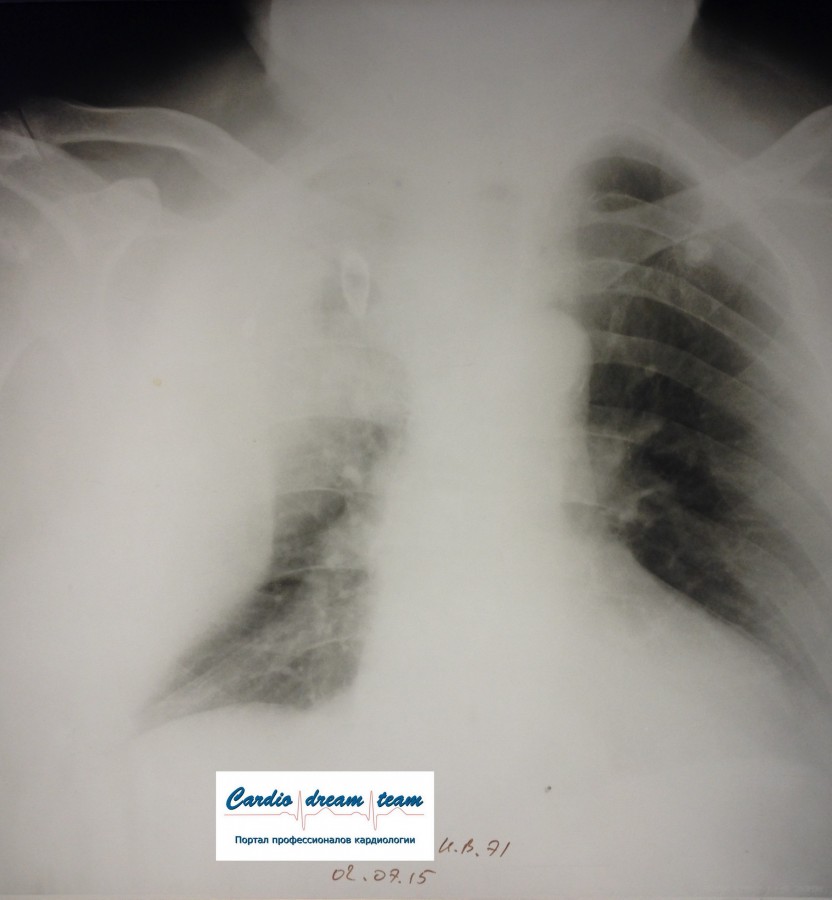

M, 71.

FullSizeRender %281%29.jpg

FullSizeRender %281%29.jpg [ 933.86 KiB | Просмотров: 17595 ]